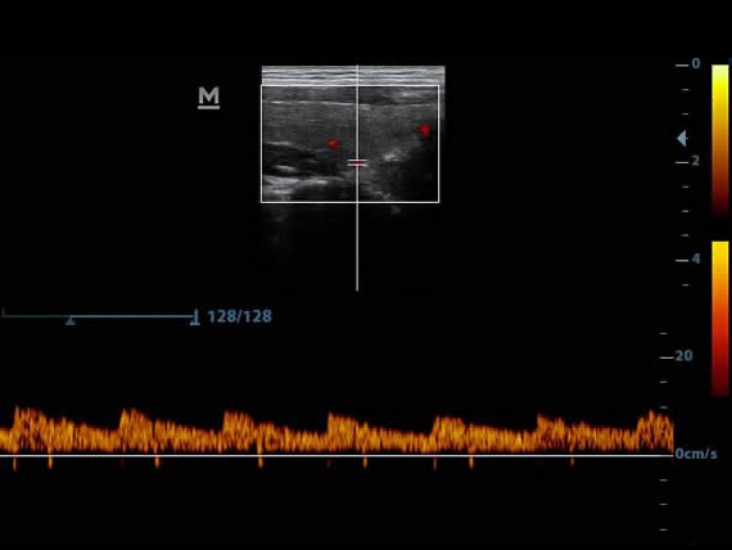

Power

Power Doppler membantu mengidentifikasi aliran darah dalam kondisi klinis yang berbeda, yang penting untuk membantu menetapkan lokasi pembuluh darah, mempermudah pengukuran secara akurat.